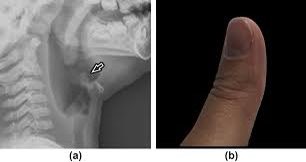

📍croup (steeple sign)

📍Acute epiglottis (thumb sign)